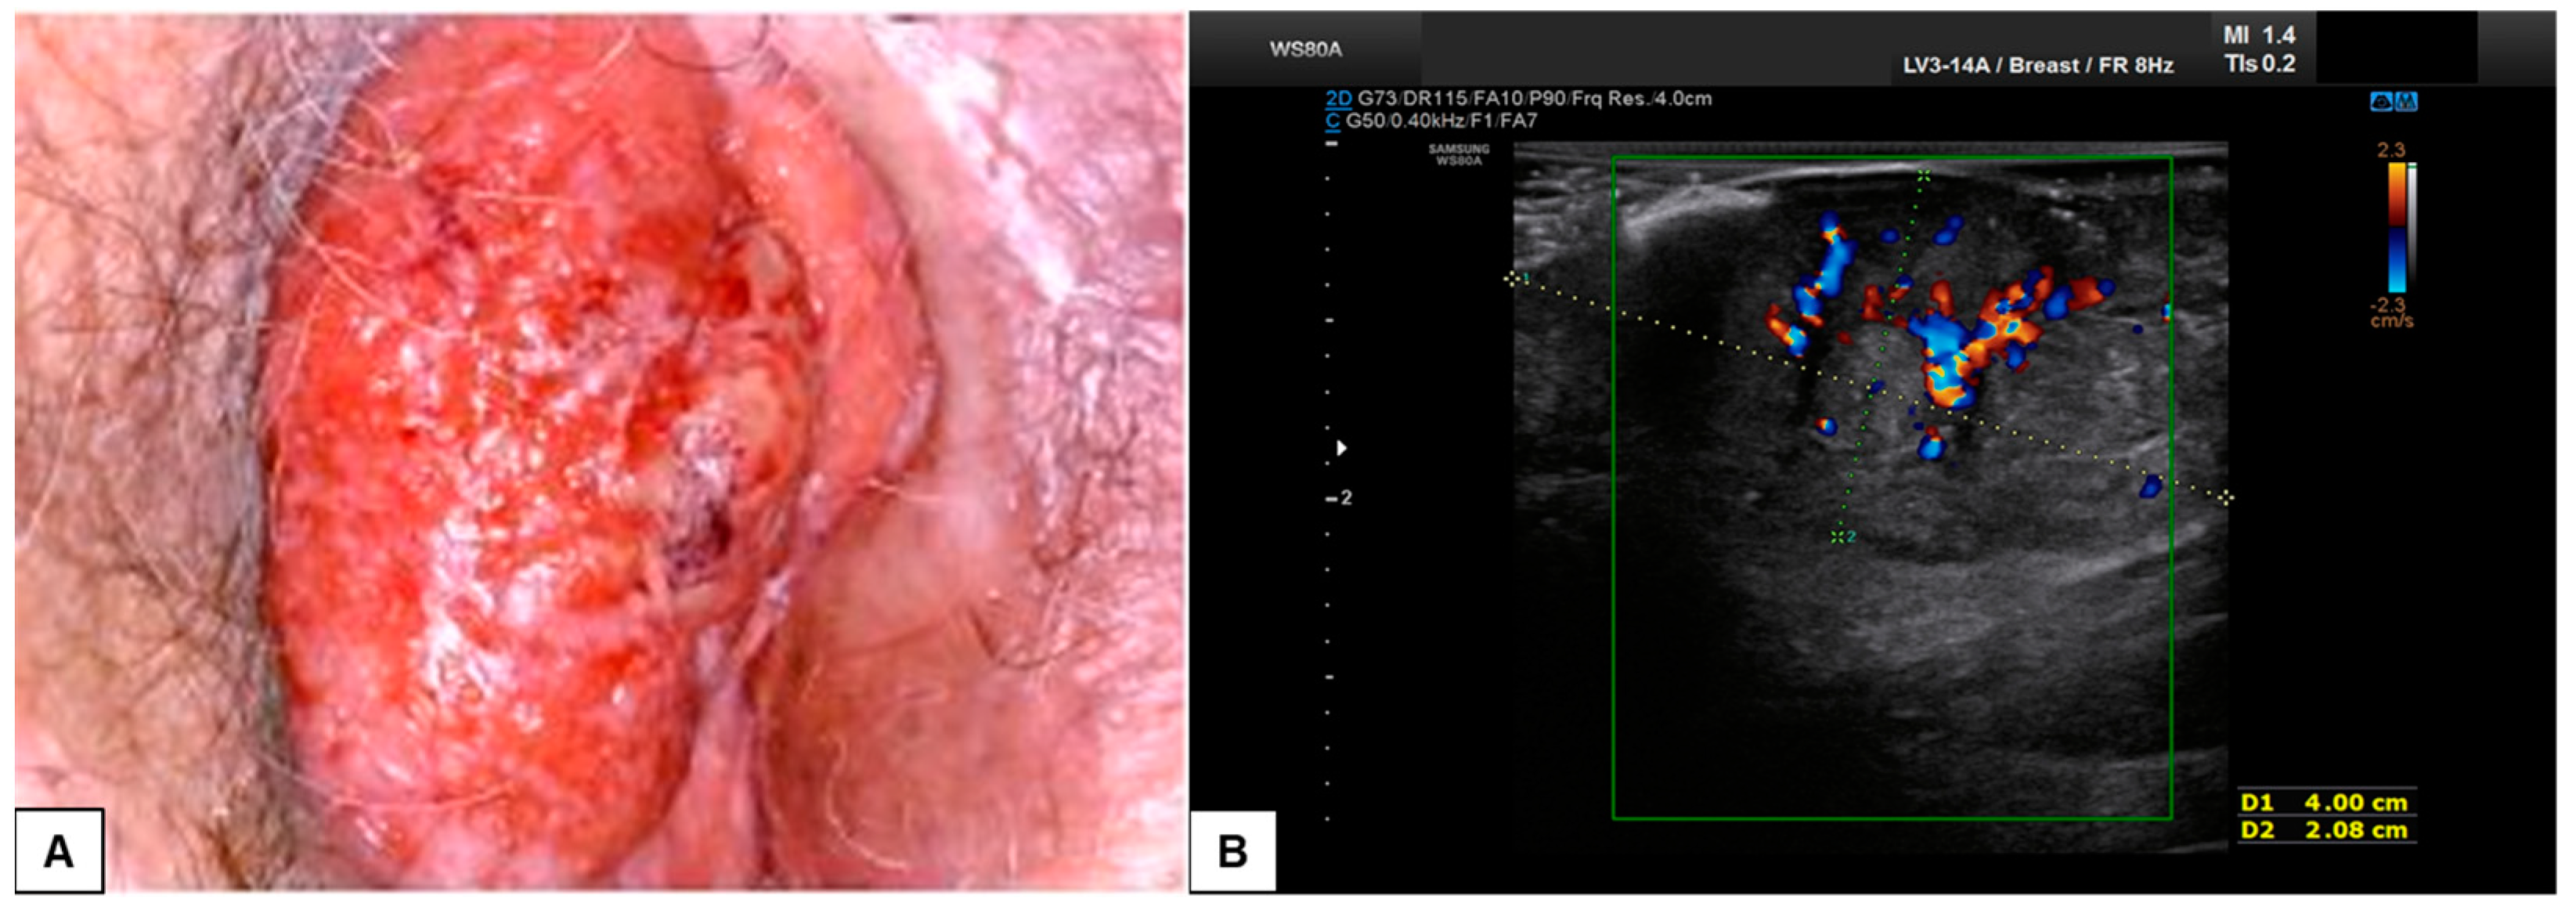

7.3. Malignant Vulvar Lesions